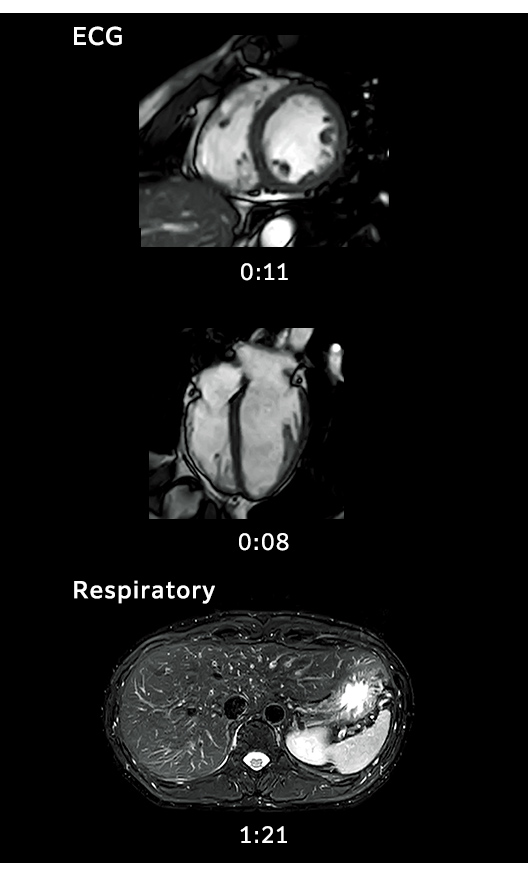

IP-RAPID, iteratif işleme kullanılan yüksek hızlı görüntülemedir ve IP-RAPID uygulanmayan geleneksel görüntüleme yöntemleriyle benzer görüntü kalitesini korurken tarama sürelerini %60’a kadar azaltır.

Yüksek Hızlı Ön Tarama